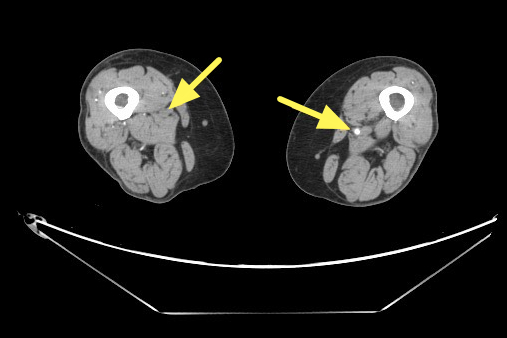

楊凱迪近期診治一位64歲長期洗腎的女性患者,數月來反覆出現下肢刺痛,夜深與洗腎後特別明顯,同時右小腿與腳踝各有一處約3×5公分久未癒合的慢性傷口。整形外科醫師清創時發現傷口幾乎沒有出血,轉介心臟血管外科,經「踝臂血壓指數(ABI)檢查」左右腳分別為僅約0.67及0.64,代表下肢血流循環不良。電腦斷層血管攝影更顯示雙側股動脈及膕動脈嚴重狹窄。

醫療團隊與患者溝通後,決定採行「微創導管血管內介入治療」,目前的血管內治療,除了常見的血管內氣球擴張與支架放置,亦可使用「機械式除栓裝置」,清除血管壁上的鈣化斑塊。搭配「血管內超音波(IVUS)」提供斑塊的即時三維影像,協助醫師精準定位斑塊方位。楊凱迪解釋,傳統氣球擴張術雖能推開斑塊,但術後易再狹窄,若能清除斑塊,再使用「塗藥氣球」或「塗藥支架」維持血管管徑,可有效維持血管長期通暢。相較傳統除栓手術需大範圍切開整條血管相比,微創導管僅需2至3毫米的穿刺傷口,傷口極小,對高齡、洗腎或多重慢性病患者,提供更安全有效的選擇。